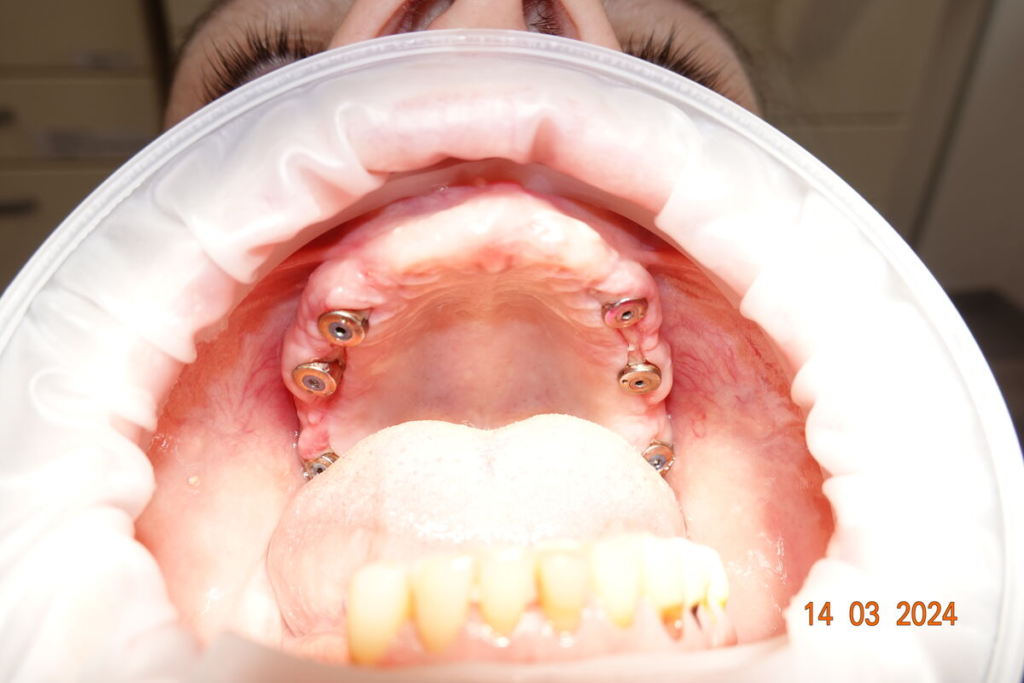

Technika All-on-X — II. fáze

- 4–6 implantátů metodou All-on-X

- digitální otisky pro rychlou výrobu zubů